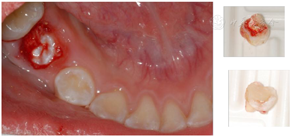

行囊肿开窗减压术:局麻下拔除85,扩大拔牙窝,生理盐水冲洗,囊腔内置入碘仿纱条1根,每周换药(图4)。共换药2个月;局麻下拔除16。